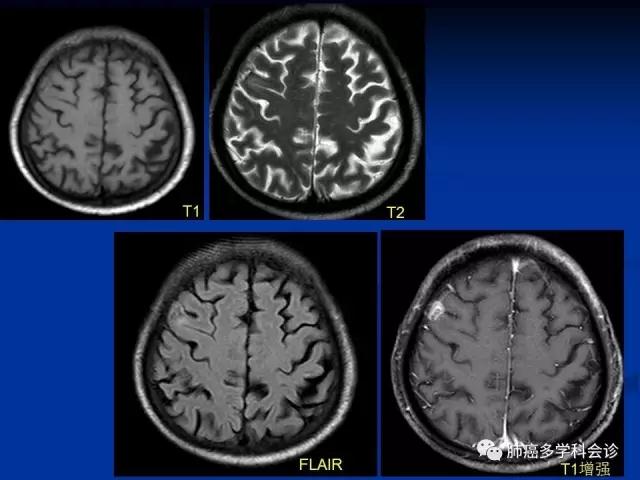

多数脑转移瘤的常规影像学表现具有一定的特征性,如“小病灶,大水肿”或呈脑内多发病灶

然而,在日常工作中常常会出现一些非典型表现的转移瘤,如单发的、不伴周围水肿的,部分脑转移患者可无明确原发肿瘤病史,对疾病的确切诊断带来困扰

常规MRI序列,主要包括T1、T2、FLAIR及增强Tl等,所显示的是病变的含水量和对比剂透过受损的血脑屏障进入病灶等情况

MRI弥散加权成像依靠不同组织间水分子弥散差异性造成的图像信号衰减来反映组织的结构特性

提供了与以往Tl、T2不同的新的成像对比,可反映病理状态下组织内水分子运动状态的异常改变

成为临床早期发现、有效鉴别病灶的重要辅助手段